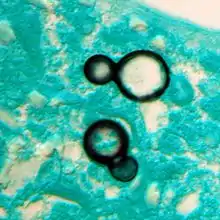

Once suspected, the diagnosis of blastomycosis can usually be confirmed by demonstration of the characteristic broad based budding organisms in sputum or tissues by KOH prep, cytology, or histology.[27] Tissue biopsy of skin or other organs may be required in order to diagnose extra-pulmonary disease. Blastomycosis is histologically associated with granulomatous nodules.

Large yeast-like fungi seen within giant cells at arrows. Budding yeasts in cytoplasm of giant cells at arrows. Broad-based budding and double contoured cell wall seen in the giant cell in the center is characteristic of Blastomyces dermatitidis.